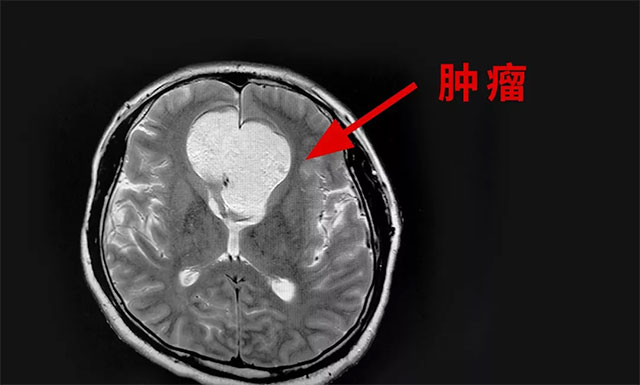

▲ 影像显示肿瘤有拳头大小

头颅磁共振检查显示,额部(中线处)见团状异常信号灶,矢横高径约5.8*5.5*5.4cm,周围脑实质受压移位,肿块向鞍内生长。

由潘仁龙主任、李士其教授、吴治群博士组成的专家组会诊后考虑为颅内胆脂瘤,并且患者颅内肿瘤变性坏死破裂进入脑室,造成了化学性脑室炎,使患者产生颅内高压症状(即刻腰穿,压力高达330mmH2O),诱发癫痫发作。专家组认为,患者病情加重,需尽快手术,缓解颅内高压症状,抑制癫痫发作,尽快缓解病情,挽救患者生命。